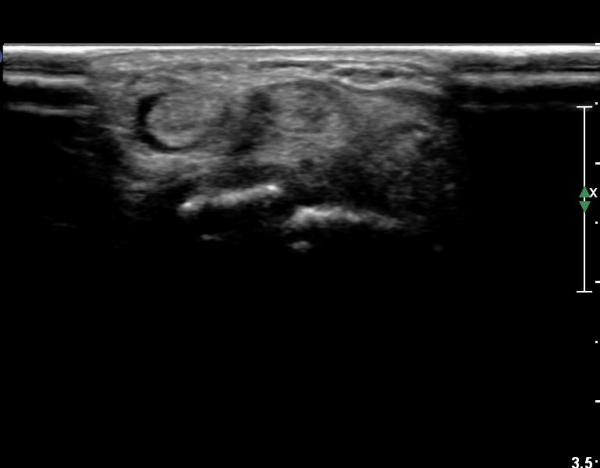

¼Õ¸ñ µî Áß¾Ó¿¡¼­ ¼Õ°¡¶ô ½ÅÀü°Ç Á¾´Ü¸é °Ë»ç¿¡¼­ ƯÀÌ ¼Ò°ßÀ» º¸ÀÌÁö ¾Ê´Â´Ù(»çÁø 1)